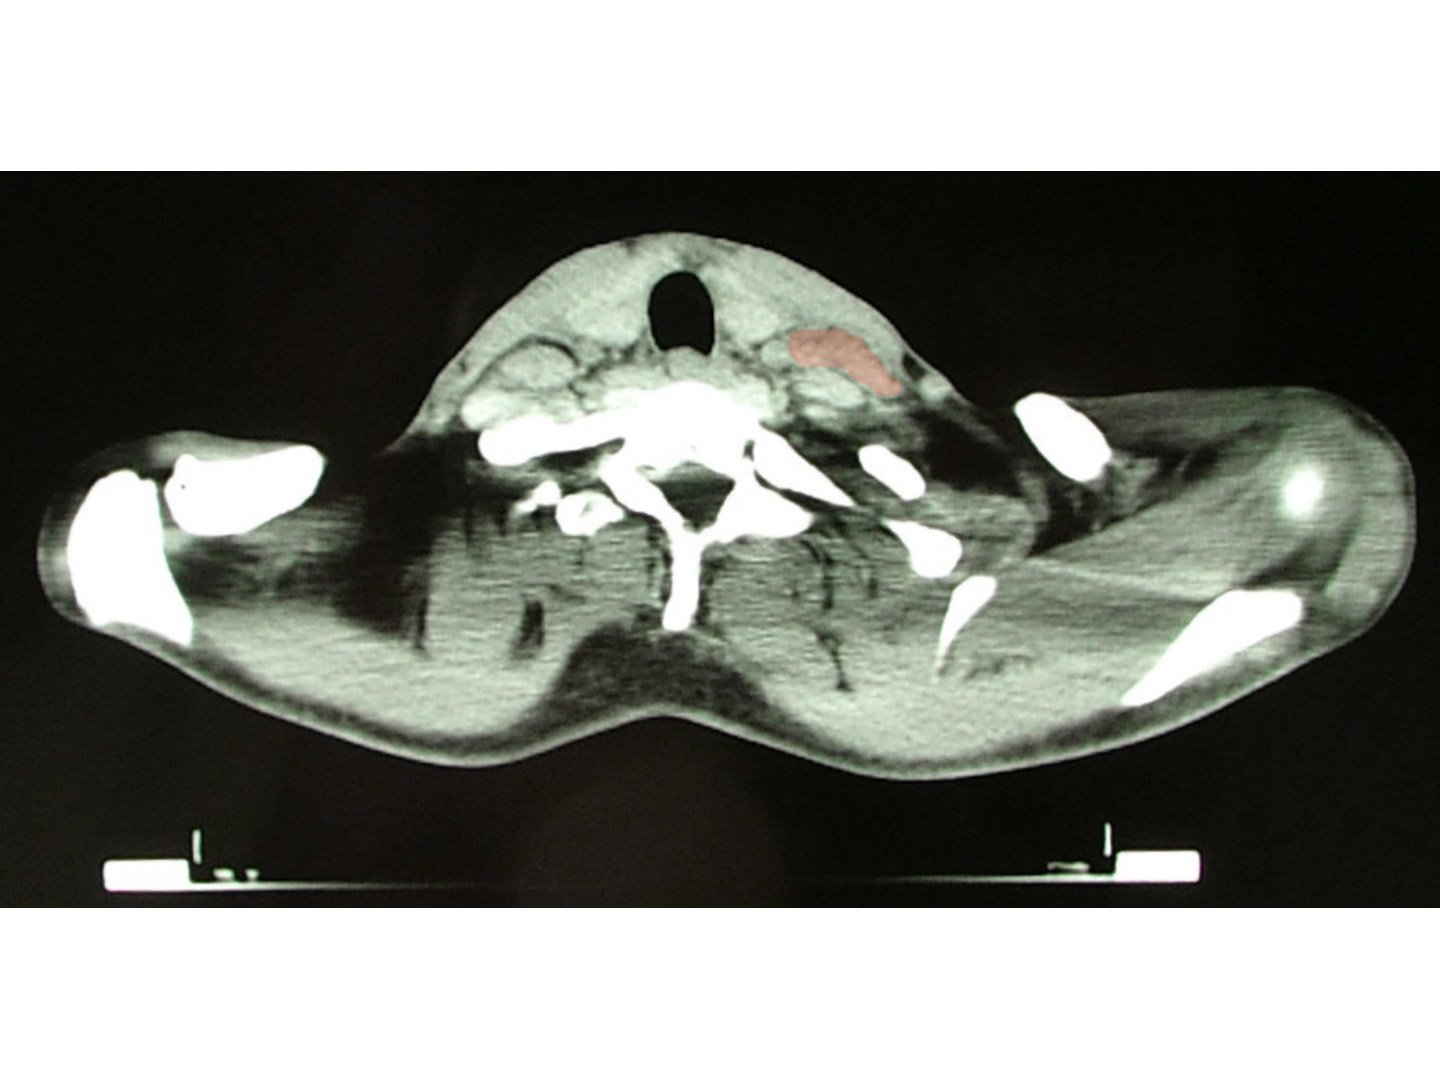

Die Lymphknotenschwellung bei M. Hodgkin ist im Gegensatz zu benignen LK-Schwellungen schmerzlos ([[Abb. 32119]]). Die malignen Lymphknotenpakete sind mit ihrer Umgebung verbacken und kaum verschieblich. Sie befinden sich vor allem cervikal, mediastinal und selten abdominal ([[Abb. 32120]]).